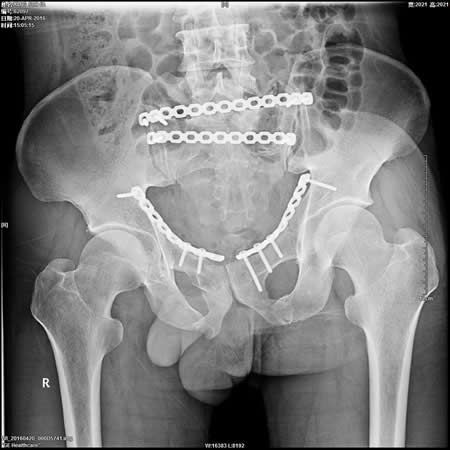

5、骨盆骨折切开复位内固定手术。